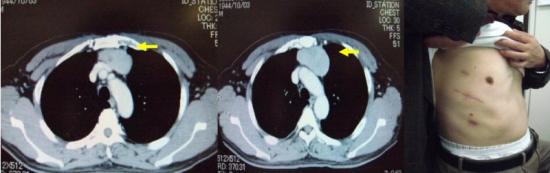

左肺癌の画像所見

胸部XP(左上肺野に腫瘤影あり)

胸部CT